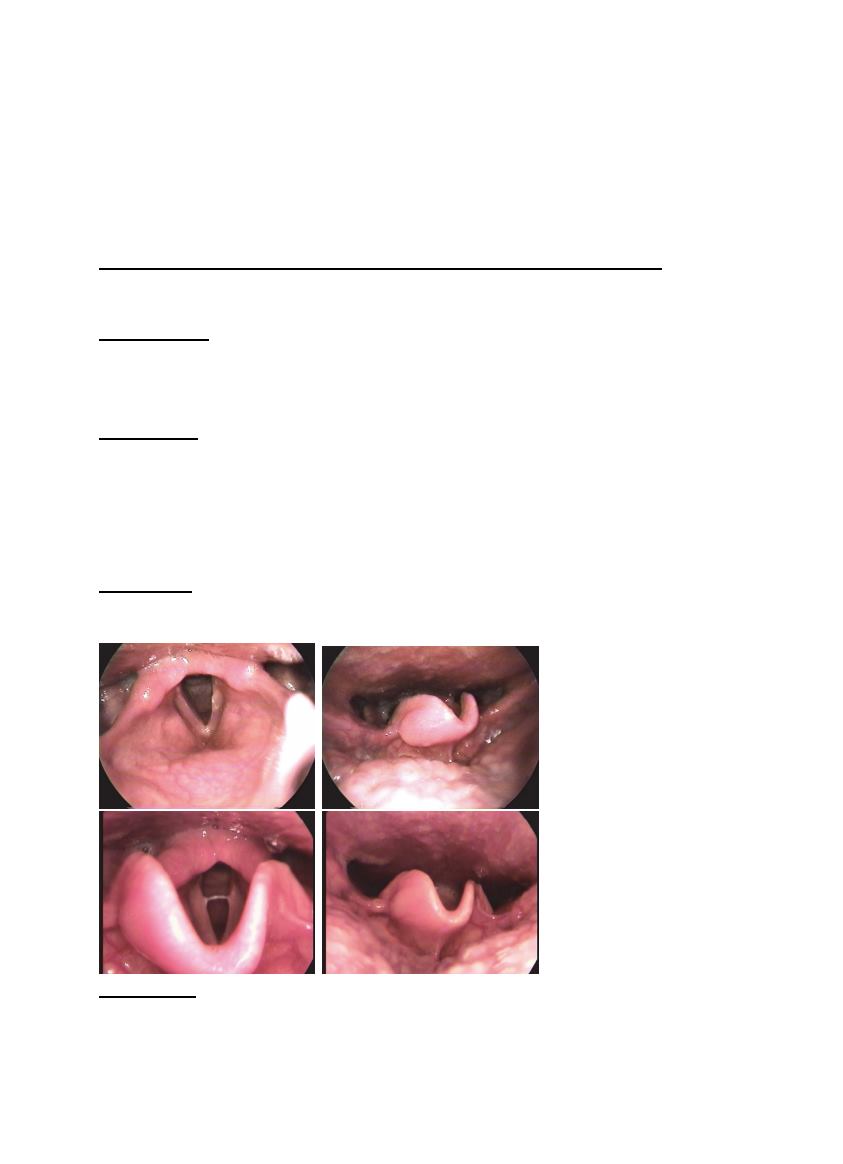

Descripción: aumento de volumen con aspecto de quiste de retención,

de cerca de un cm de diámetro mayor, ubicado en epiglotis desde borde

libre hacia cara lingual. Pliegues vocales difusamente congestivos con

leve edema subcordal. Aritenoides edematosos con aspecto redondeado

congestivo del ápex y edema retroaritenoídeo.

Conclusión:

Lesión de epiglotis ¿quiste de retención?; Laringitis por

reflujo faringolaríngeo leve.

Comentario: persiste aspecto de edema de aritenoides sin síntomas de

reflujo, pero el quiste parece reducirse espontáneamente.

Abajo, año 2015

diez años de

seguimiento,

lesión parece de

menor tamaño.